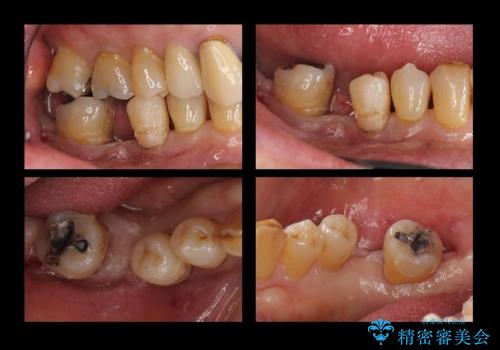

60代男性 奥歯のブリッジ 倒れこんでいる奥歯を部分矯正

- 右下の親知らずが咬むと痛いとのことでした。

親知らずを抜いて、倒れこんでいる手前の歯を矯正治療で移動させ、ブリッジにしました。

矯正治療をしなければ、倒れこんでいる影響で手前の奥歯も含めて歯周病で悪化してしまうため、しっかり起こして治療をしました。

60代でしたが、歯もしっかり動いてブリッジを入れることができました。